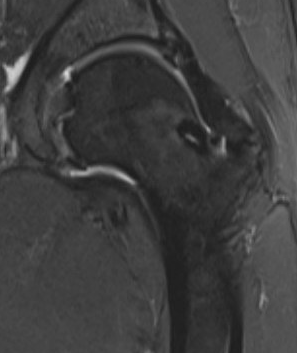

MRI

- Low signal on T1 and T2

- Do not enhance with contrast